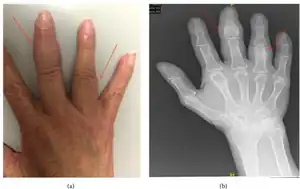

| Examination findings and radiograph illustrating periostitis of the right hand | |